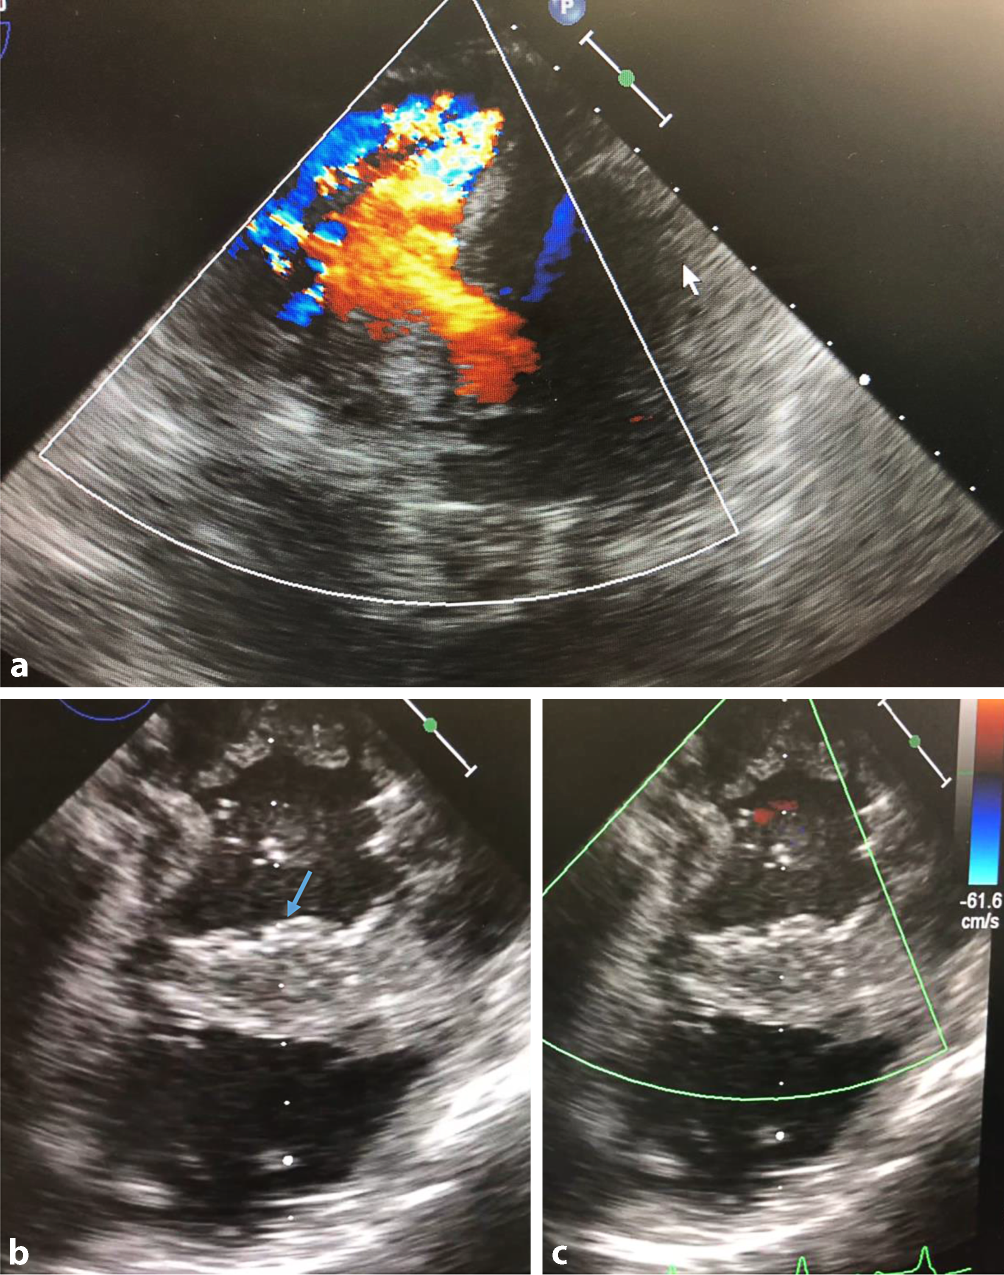

Echokardiographie bei großem Infarkt-Ventrikelseptumdefekt (VSD). a Infarkt-VSD mit großem Shunt im Farb-Doppler. b und c Zustand nach operativer Behandlung mit Exklusionspatch (blauer Pfeil, b). Im Farb-Doppler ist kein Shunt mehr detektierbar (c)

Abb. 3

Operativer Situs bei Infarkt-Ventrikelseptumdefekt (VSD) bei Hinterwandinfarkt. a Situs nach Ventrikulotomie durch Infarktareal. Blauer Pfeil zeigt auf Infarkt-VSD. b Z. n. dem Einnähen eines Exklusionspatches aus bovinem Perikard. c Verschluss der Ventrikulotomie

Abb. 2